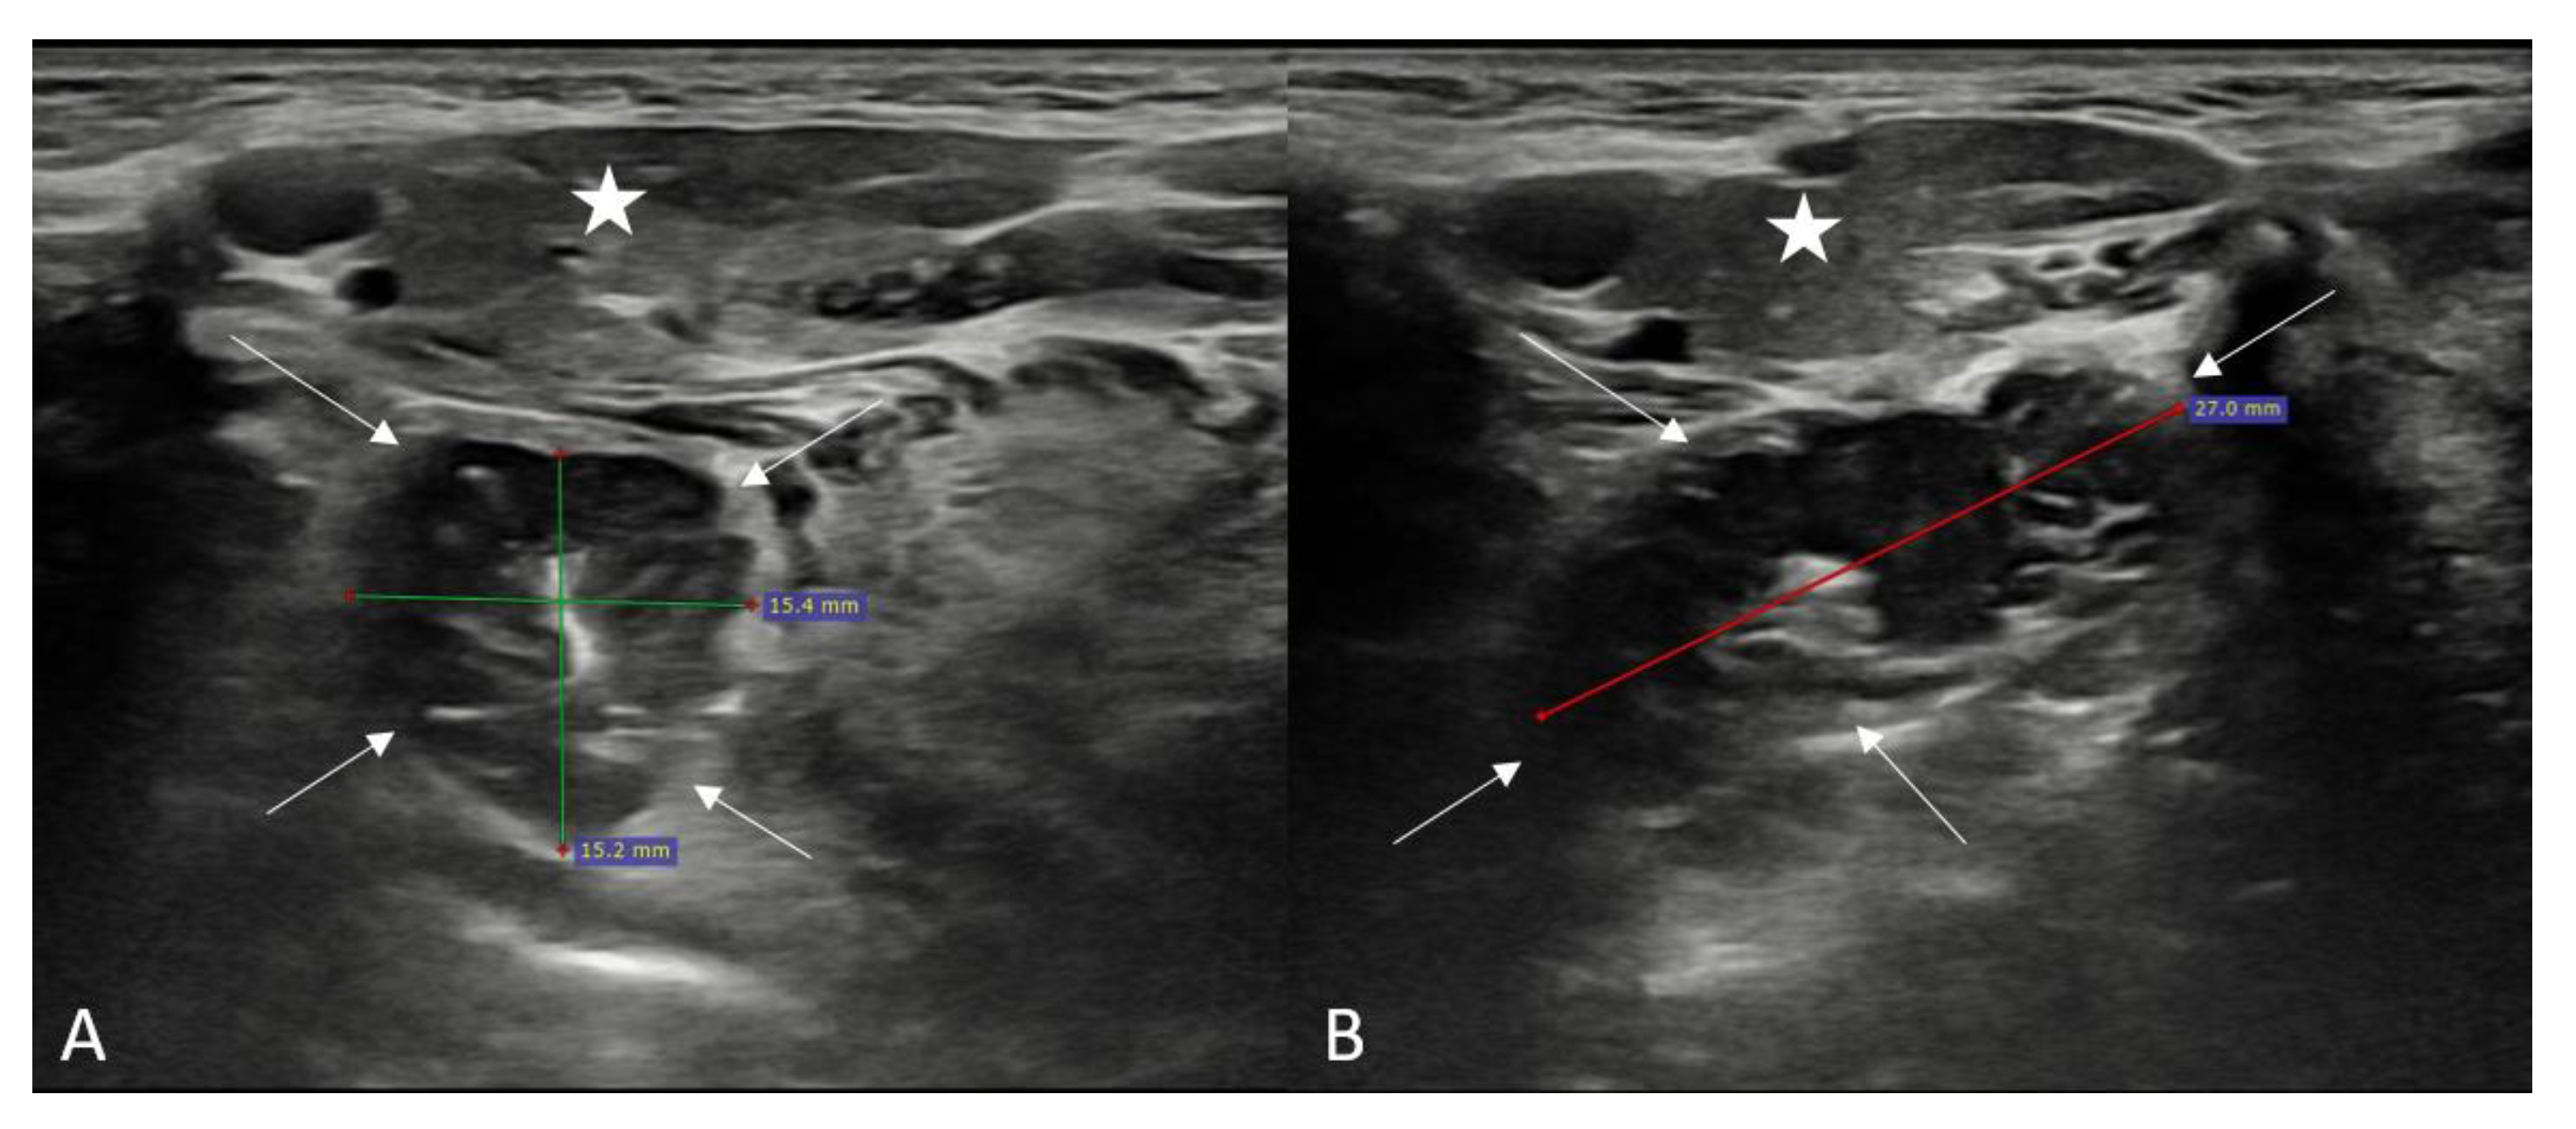

2.2. Ultrasound and Shear Wave Elastography Assessment